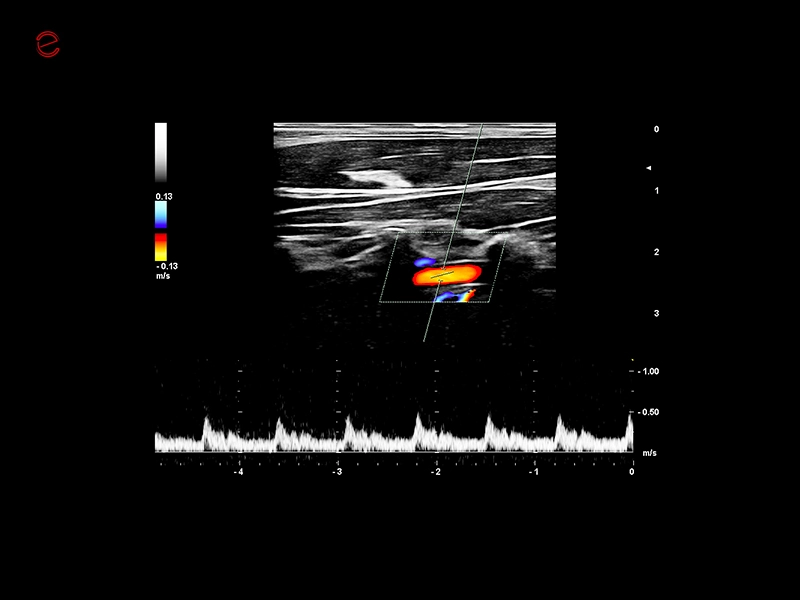

MyLab™C30 - Vertebral PW

MyLab™C30 - Vertebral PW